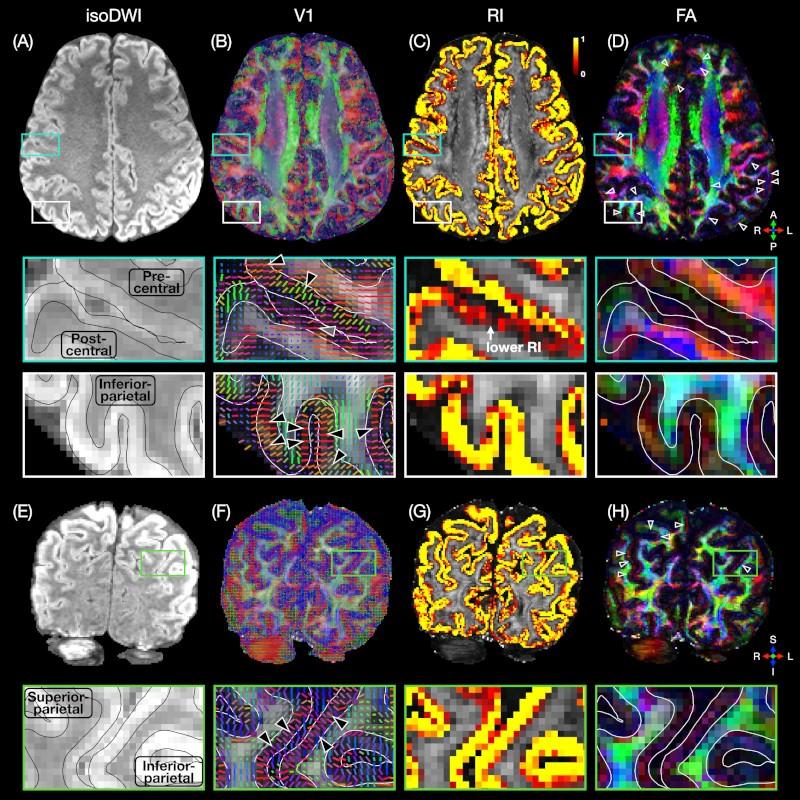

Column-based cortical depth analysis of the diffusion anisotropy and radiality in submillimeter whole-brain diffusion tensor imaging of the human cortical gray matter in vivo

BIAC researchers led by Yixin Ma and Trong-Kha Truong, along with Iain Bruce, Jeff Petrella, and Allen Song, have published a column-based cortical depth analysis of the diffusion anisotropy and radiality in the human cortical gray matter in vivo.